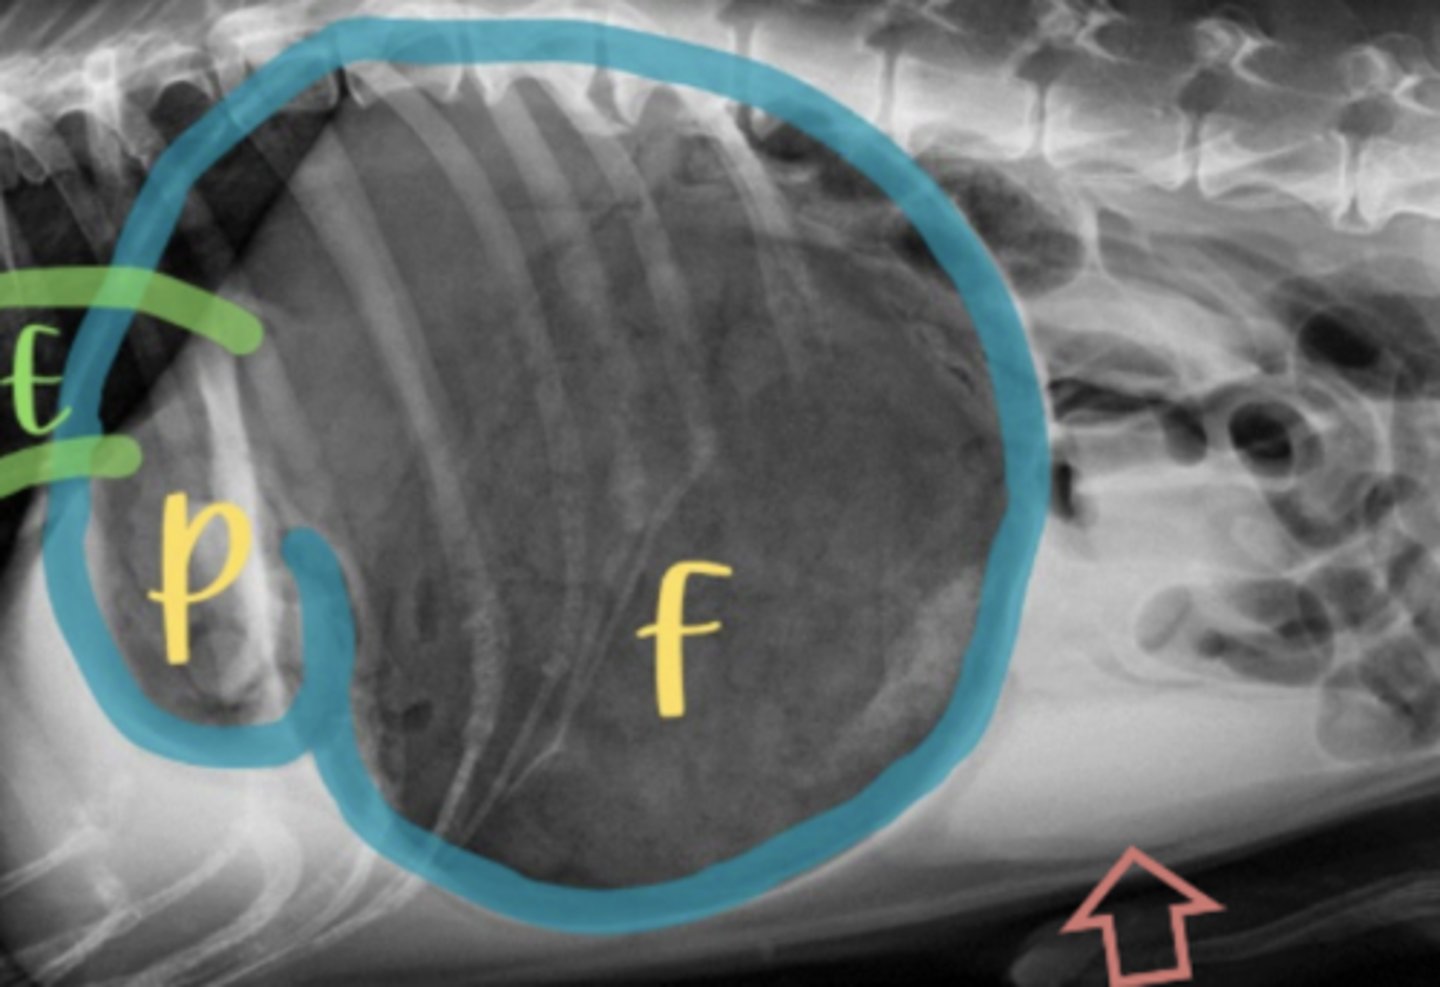

dilatación-torsión gástrica

patología: